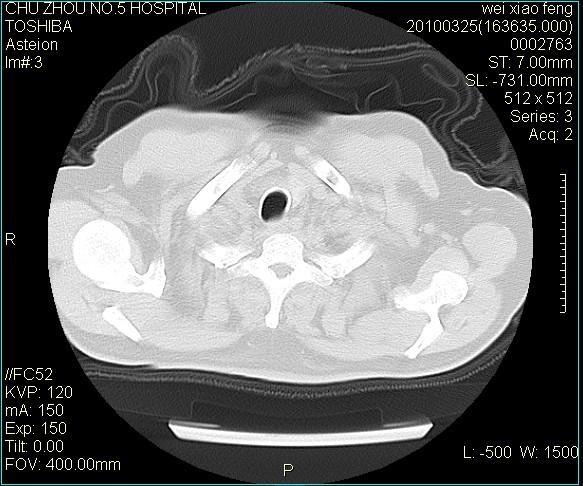

男,60岁,反复咳、痰、喘3月,加重3天。